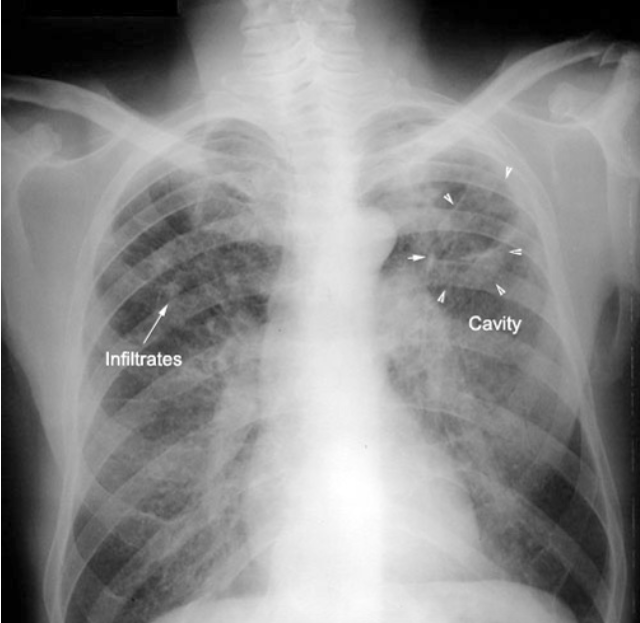

What is shown in the image?

Tuberculosis